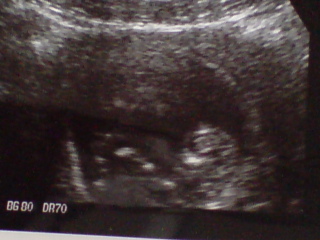

苦労して撮影した写真がコレ。

↓  ↓  ↓

20081025113904.jpg20081025113823.jpg

一生懸命足や手を動かして腹筋中。愛らしい限りなんですが。

長い事見ていても、飽きないといえば飽きないんだけど・・

その落ち着きのなさにはチョット。。

この写真を撮るのも 相当 苦労しましたよ?

モソモソ、ゴソゴソと動き回っていて

占有スペースの中で、 グルグル回転 したりしてましたヾ(- -;)ぉぉぉぃ